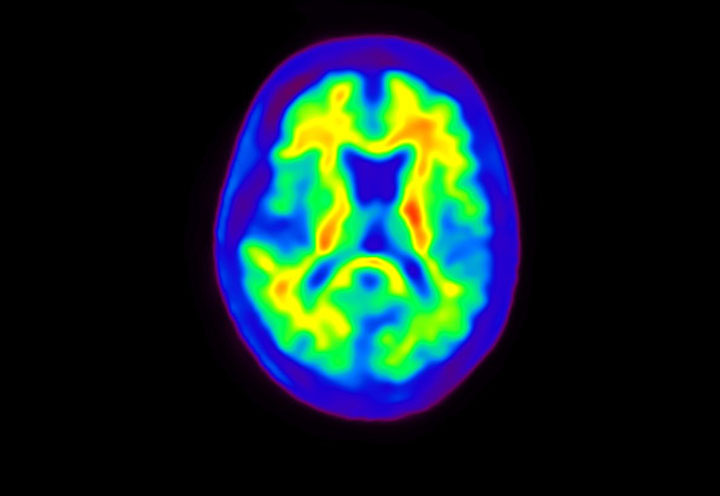

Head / Case4 : Amyloid

Courtesy : Kindai University Hospital

- Imaging protocol

- Injected dose: 3.21 MBq/kg, 18F-Flutemetamol

- Uptake time: 100 minutes

- Scan time: 20 minutes